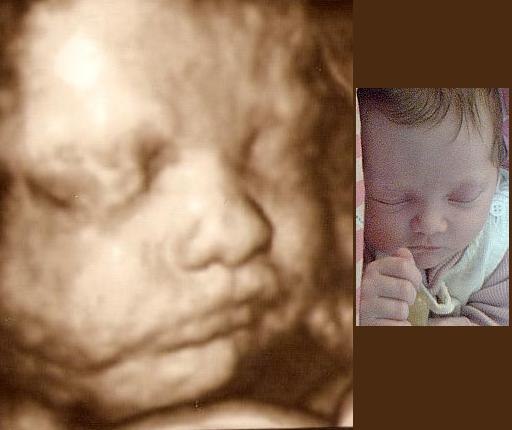

Syntes det er vildt! elsker 3d..Håber jeg kommer til at opleve det igen en dag..Peter sys det ser råklamt ud så tager bare en veninde med

Syntes oplevelsen er helt fantastisk og når man har muligheden for at lure den kage der er i ovnen..så kan jeg sgi ikk la være